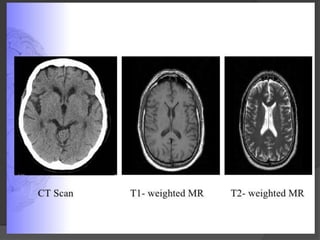

Grey-scale Appearance on CT

Tissue

Appearance

Bone

White

Calcified Tissue

Clotted Blood

Grey Matter

Light Gray

White Matter

Medium Grey

CSF

Near Black

Water

Air

Black

Points to remember



CT image is determined only by degree to which tissues absorb X-ray

Bony str. Absorb large amount of x-rays and tend to obscure the details

of neighboring structures poor visibility in brainstem.

Poor differentiation of grey-white pattern than compared to MRI.

T1 Weighted MRI

Best for visualizing normal

neuroanatomy

Sharp boundaries between

grey matter, white matter, and

Useful in evaluation of

cerebro-pontine angle cistern

& pituitary fossa

Bone white

white matter light grey

grey matter medium grey

water/CSF/air- Black

T2 Weighted MRI

Less distinct boundaries

between white and grey matter

Best for displaying pathology

Useful in demyelination, edema

& tumour infiltration

Gray matter medium gray

white matter dark grey

CSF and water White